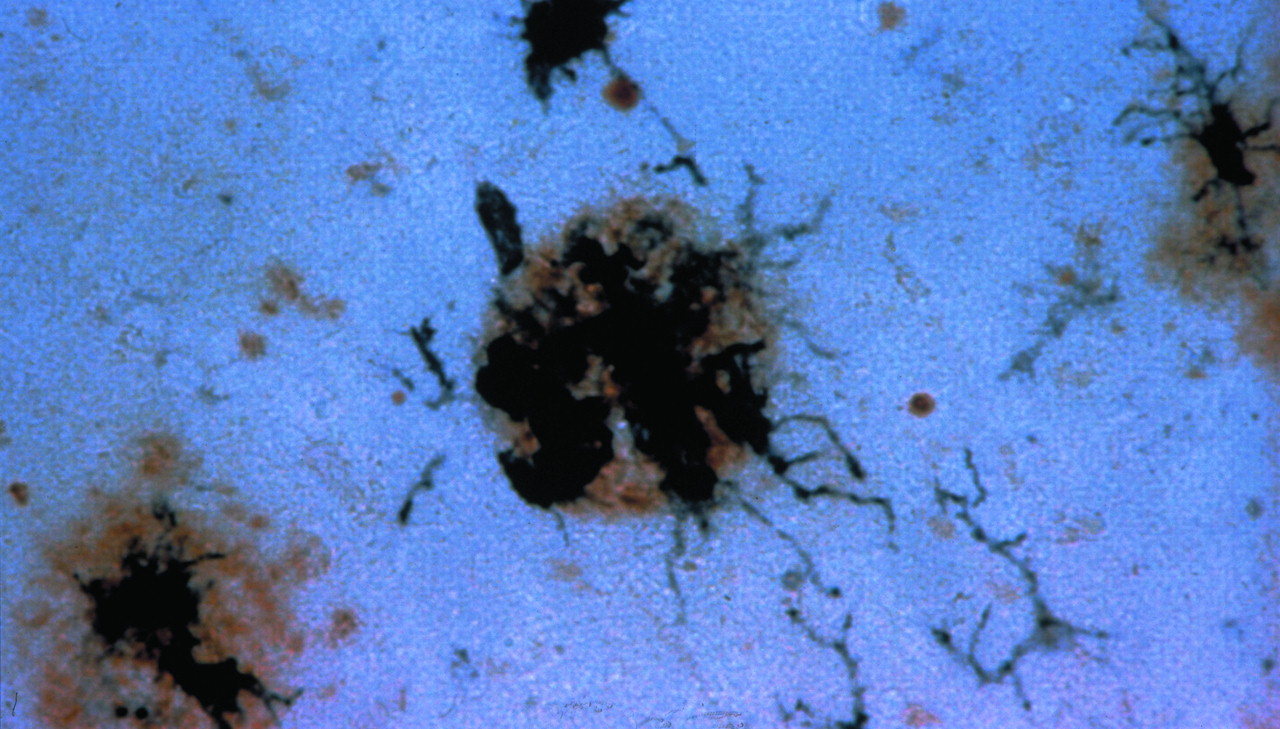

Immunohistochemical staining of activated microglia clustered around a senile plaque. Senile plaques are stained brown with the use of an antibody specific for the ß-amyloid protein. Antibody specific for a membrane protein expressed by activated microglia develop a dark purple color in the staining reaction.